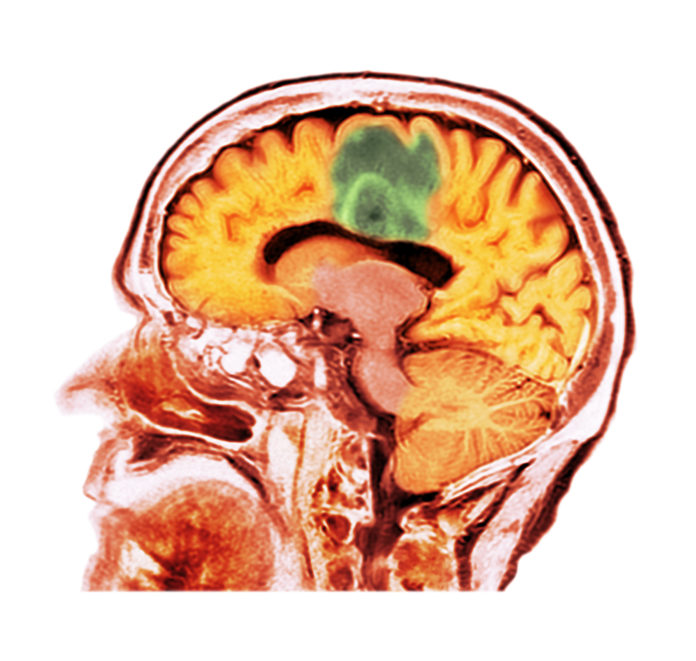

It is well established that glioblastomas are one of the deadliest brain cancers with a median survival rate of about 15 months, according to one estimate. Now new research led by scientists at the University of Sydney could help explain why glioblastomas recur after treatment. Details of the work are reported in a new Nature Communications paper titled “Histone methyltransferase PRDM9 promotes survival of drug-tolerant persister cells in glioblastoma.”

Glioblastomas account for about half of all brain tumors and an estimated 200,000 deaths globally. Tumor recurrence is almost universal even after treatment with surgery, radiation, and chemotherapy. According to the current study, during chemotherapy, persister cells in glioblastoma hijack PRDM9, a gene that is typically active in reproductive cells at the very start of egg and sperm formation, to generate cholesterol which helps them withstand the damage.Â